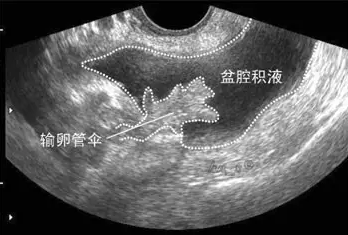

盆腔積液大多是盆腔存在炎性滲出物,常表現為小腹下墜、脹痛,腰酸腰痛、月經紊亂、不孕等,那具體盆腔積液是怎么引起的呢?盆腔積液是怎么回事?盆腔積液的危害有哪些?盆腔積液的產生主要可分為生理性因素和病理性因素兩種。

生理性盆腔積液是指正常的盆腔積液,不需要治療。人體的盆腔、腹腔并不是干巴巴的一塊「土地」,腹膜、大網膜、腸管等都會分泌一些液體,這些液體通常起到潤滑和保護盆腹腔器官和組織的作用。盆腔積液可通過 B 超檢查觀察到,如果積液的深度小于 3 cm,沒有其他不舒服的癥狀,通常是不需要處理的。

不孕是盆腔積液最常見的癥狀。如果盆腔炎導致輸卵管堵塞,就會出現不孕。